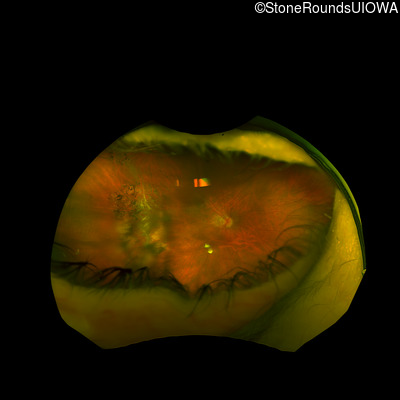

Age at visit: 32 years